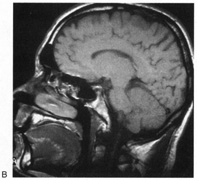

Fig. 9. Macular-sparing striate hemianopia. A 49-year-old woman with headache and difficulty seeing to the left for 1 week. A. Fields show left hemianopia that spares a small zone around the central fixation spot. B. Magnetic resonance imaging shows infarct of right striate cortex, with sparing of occipital pole. (From Rosen ES, Eustace P, Thompson HS, Cumming WJK [eds]: Neuro-Ophthalmology. London: Mosby, 1998.)

Partial lesions of the striate cortex are frequent. With posterior cerebral infarcts, a macula-sparing hemianopia occurs in patients with adequate collateral circulation of the macula region (occipital pole) from the middle cerebral artery (Fig. 9).35 Previously, macula-sparing was thought to result from bilateral representation of a small stripe flanking the vertical meridian, which expanded to as much as 3° at the fovea.41 However, studies of monkey V1 do not find bilateral representation of the hemimaculae,42 and computed tomography (CT) and magnetic resonance imaging (MRI) studies in humans with hemianopia document the correlation of macular sparing with sparing of the occipital pole.43,44 Also, careful perimetry of hemianopes with the scanning laser ophthalmoscope shows that, although there is a slight overlap from the seeing field into the blind field along the meridian, macular sparing of 2° to 5° is only present in some patients.45,46 Therefore sparing more likely reflects the extent of occipital pathology than retinal anatomy. Macula-sparing has some localizing value, because it is seen mainly with lesions of striate cortex.